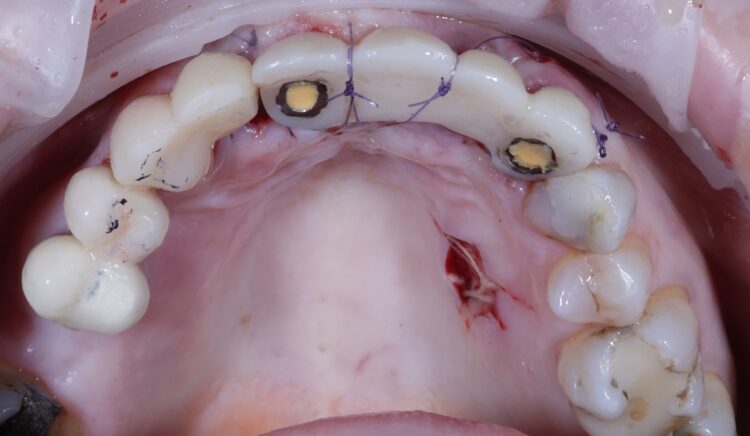

A miniflap was raised in the upper central region for this case to enhance visualisation for implant placement and augmentation. The guide was placed in the mouth and the standard guided surgery drilling protocols were followed. The new surgical kit improves workflow and intraoperative efficiency with the removal of spoons and a guide adaptor allowing for both guided and freehand use. During this step of the procedure, the guide was temporarily removed to double check the drilling angulation and verify this lined up with the pre-fabricated temporary bridge.

The two 3.3mm diameter Tapered Pro Conical implants were then placed through the guide at the pre-determined positions, angles and depths. Both implants achieved an insertion torque above 30Ncm.

Bone grafting was then performed, placing MinerOss X (BioHorizons Camlog) into the extraction sockets and the jump gap around the implant in the UL3 socket, to preserve the existing bone of the socket. This would help to minimise changes in the bone post-surgery and help to maintain the buccal profile of the ridge. The biomaterial is a bovine bone mineral matrix that has been proven to increase vertical bone height alongside implant placement.[vi] It has worked very well in my cases to date, offering a high turnover to bone for maximum stability and efficient results with immediate implant protocols.

A soft tissue graft was then performed, harvesting connective tissue from the palate and placing it in the sulcus of the UL3.

Non-engaging cylinders were placed onto the implants to connect to the pre-fabricated temporary bridge. A premade temporary bridge was connected, contoured and polished, with particular attention paid to the contour of the restoration and suturing with the aim of prosthetically guided soft tissue healing.